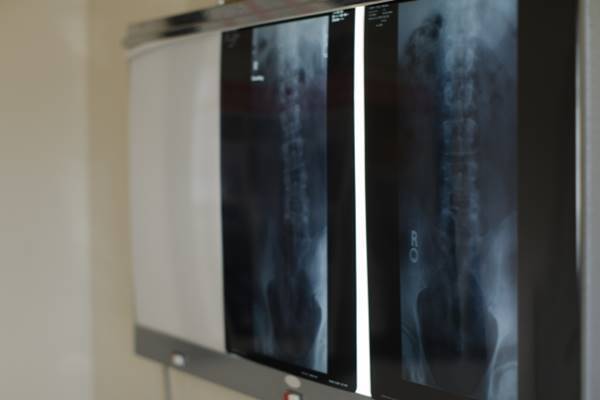

【ケース1】レントゲンを見てびっくり!“黒い影”の正体は1カ月分の便だった

「1カ月排便がないんです」と、真っ青な顔をして来院した70代男性。本当に1カ月も排便がないのか、半信半疑で質問しながら「もしかしたら認知症の症状が出ているのかもしれない」と鳥居先生は思ったが、お腹のレントゲンを見れば一目瞭然、大腸に便がぎっしり詰まっていた。

「しっかりレントゲンに便の影が映っていました。それで応急処置として浣腸をし、腸に詰まっている便の排出を試みたのです。市販の浣腸薬では安全性に配慮して15~30ミリリットルと内容量が少なく、腸の蠕動運動を促すだけで全部は出しきれません。それにくらべて病院で使う浣腸は、120ミリリットルと量が多く、大腸の奥まで薬が行き届きます」(鳥居先生・以下同)